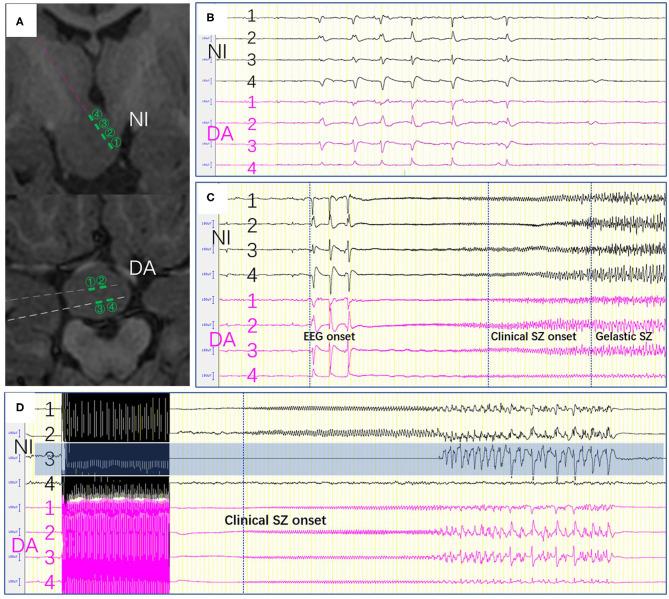

Giant hypothalamic hamartomas (HHs) are extremely rare lesions, for which the treatment is challenging. While minimally invasive treatments such as radiofrequency thermal coagulation and laser ablation have improved seizure outcomes, multiple operations are often required. This study investigated the value of one-stage stereo-array radiofrequency thermocoagulation based on stereotactic electroencephalography (SEEG) for pediatric giant HHs. We analyzed the clinical data of six patients with giant HHs (masses with a maximum diameter >30 mm) who underwent stereotactic electrode implantation between November 2017 and April 2019. After a multidisciplinary discussion, we designed a high-density focal stereo-array electrode implantation strategy. SEEG-guided bipolar coagulations were performed between two contiguous contacts of the same electrode, or between two adjacent contacts of different electrodes. Among the six patients, three were male and three were female, with an average age of 5.08 ± 4.73 years (range, 1.4-12 years); the average follow-up duration was 20.17 ± 5.49 months. One patient had previously undergone open surgery. Four patients had gelastic seizures, one had gelastic and tonic seizures, and one had gelastic and generalized tonic-clonic seizures. The number of implanted electrodes ranged from 3 to 7, with an average of 5.33. One patient had transient diabetes insipidus after the operation, and no child had fever or new hormone metabolisms disorder after surgery. Four patients had Engel I classification outcomes (free from disabling seizures), and two patients had Engel II classification outcomes. Although the exploration of epileptic activity and the extent of ablation are limited by the number of SEEG electrodes for the complete disconnection. One-stage high-density focal stereo-array SEEG-guided radiofrequency was safe and effective for treating pediatric giant HH patients. It can be an alternative method to treat giant HHs where LITT is unavailable.